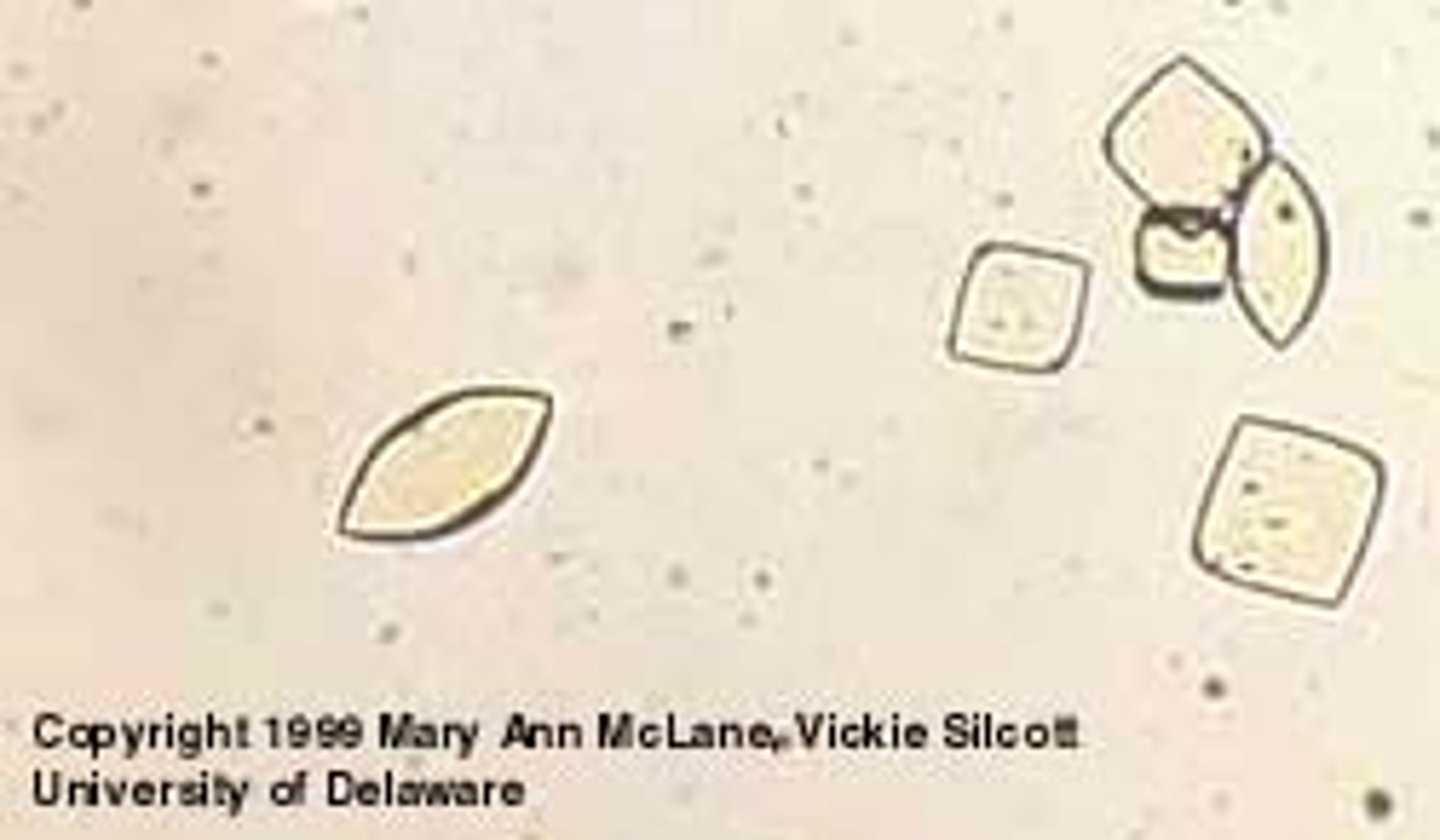

calcium oxalate crystals

urine

colorless, square with x inside

calcium oxalate monohydrate

urine

elongated, 6 sided, crystal with ends

antifreeze toxicity